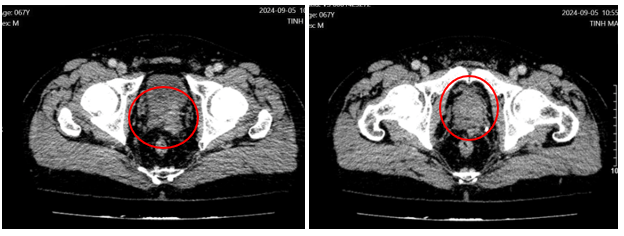

Hình 3: Hình ảnh CT tiểu khung có u tiền liệt tuyến kích thước lớn nghi ngờ xâm lấn bao, xâm lấn túi tinh bên trái, xâm lấn qua MRF, chưa đến thành trước trực tràng, nghi ngờ xâm lấn thành sau bàng quang, tổ chức thâm nhiễm vào mạc treo trực tràng.